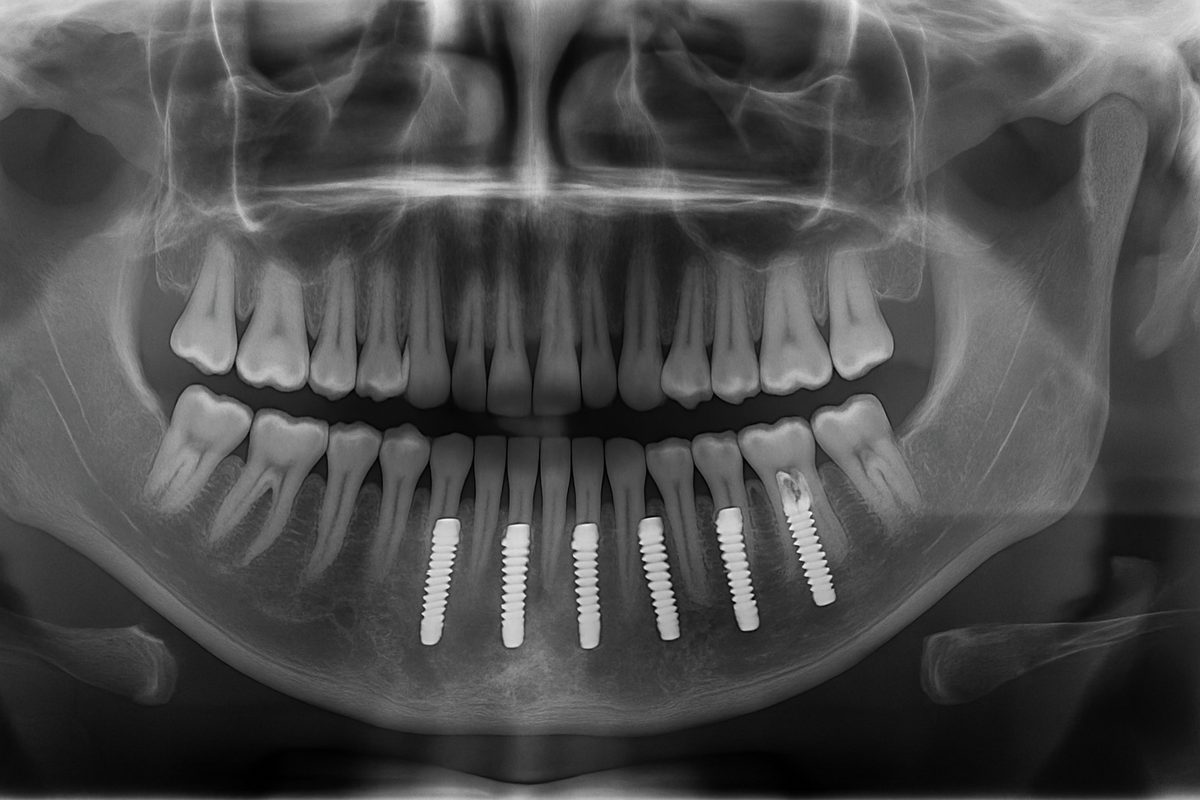

Dental implants are small titanium posts that act like tooth roots. A typical implant system has three parts: the implant (placed in the jawbone), the abutment (connects the implant to the visible tooth), and the crown (the replacement tooth you see). Unlike bridges or dentures, implants fuse with bone and do not rely on adjacent teeth for support. That makes them stable, long-lasting, and closer to natural teeth in feel and function.

First is an exam with X-rays and a CBCT scan to see bone and anatomy. Intraoral scanners (like iTero or Trios) capture precise digital impressions. This digital planning helps determine the ideal implant position and whether bone grafting is needed. The dentist will review options, timelines, and costs.